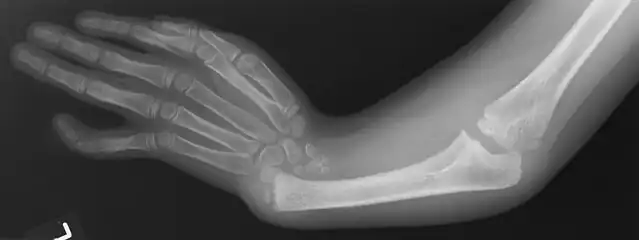

X-ray of arm showing absent radius and radially deviated hand, caused by Thrombocytopenia and Absent Radius syndrome

Radial Ray Malformations

This is characterized by hand and arm abnormalities. The following are specific characteristics:

- Malformed or absent (aplasia) thumb

- A thumb that looks more like a finger

- Partial or complete absence of a radius

- Shortening and radial deviation of the forearms

- Triphalangeal thumb

- Duplication of the thumb (preaxial polydactyly)